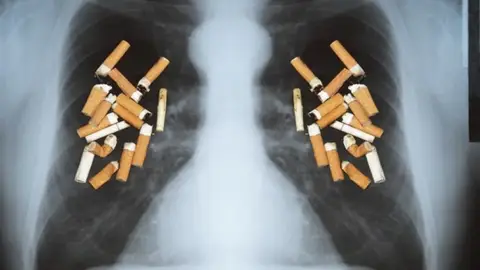

El cáncer de pulmón se incrementa en Alicante entre los jóvenes y sobre todo en mujeres a causa del consumo de tabaco

El cáncer de pulmón se incrementa en Alicante entre los jóvenes y sobre todo en mujeres a causa del consumo de tabaco

En Más de uno Alicante, con Luz Sigüenza, hemos hablado con el Dr. Padilla, ha propósito del día mundial contra el cáncer de pulmón. El neumólogo ha asegurado en Onda Cero Alicante que: "la evolución del cáncer de pulmón en España es muy preocupante, pues se trata de la primera causa de muerte por neoplasia en nuestro país. Las políticas antitabaco han modulado algo la situación, pero sigue habiendo un número muy importante de gente joven que se incorpora al tabaquismo, sobre todo las mujeres". Hasta el punto de que estamos en grave riesgo de tener una situación de urgencia, en los próximos años, de esta enfermedad oncológica en la población femenina".